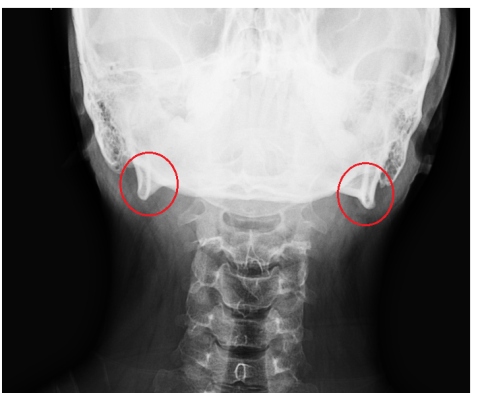

뒤통수 밑에 튀어나온 이 뼈 이름이 뭔가요?

빨간색 동그라미 안에 저 뼈 이름이 뭔가요?

occipital condyle 이 엑스레이상 으로 관찰되고 있는 것으로 사료됩니다. /

유양돌기(mastoid process)라고 불리는 부위입니다.

정상적인 구조물이니 너무 걱정하지 않으셔도 되겠습니다. 사람마다 모양차이가 있을 수 있습니다.

뒤통수 보다는 양측 턱뼈일 가능성이 높겠습니다.

의학용어로는 mandible이라고 부릅니다.